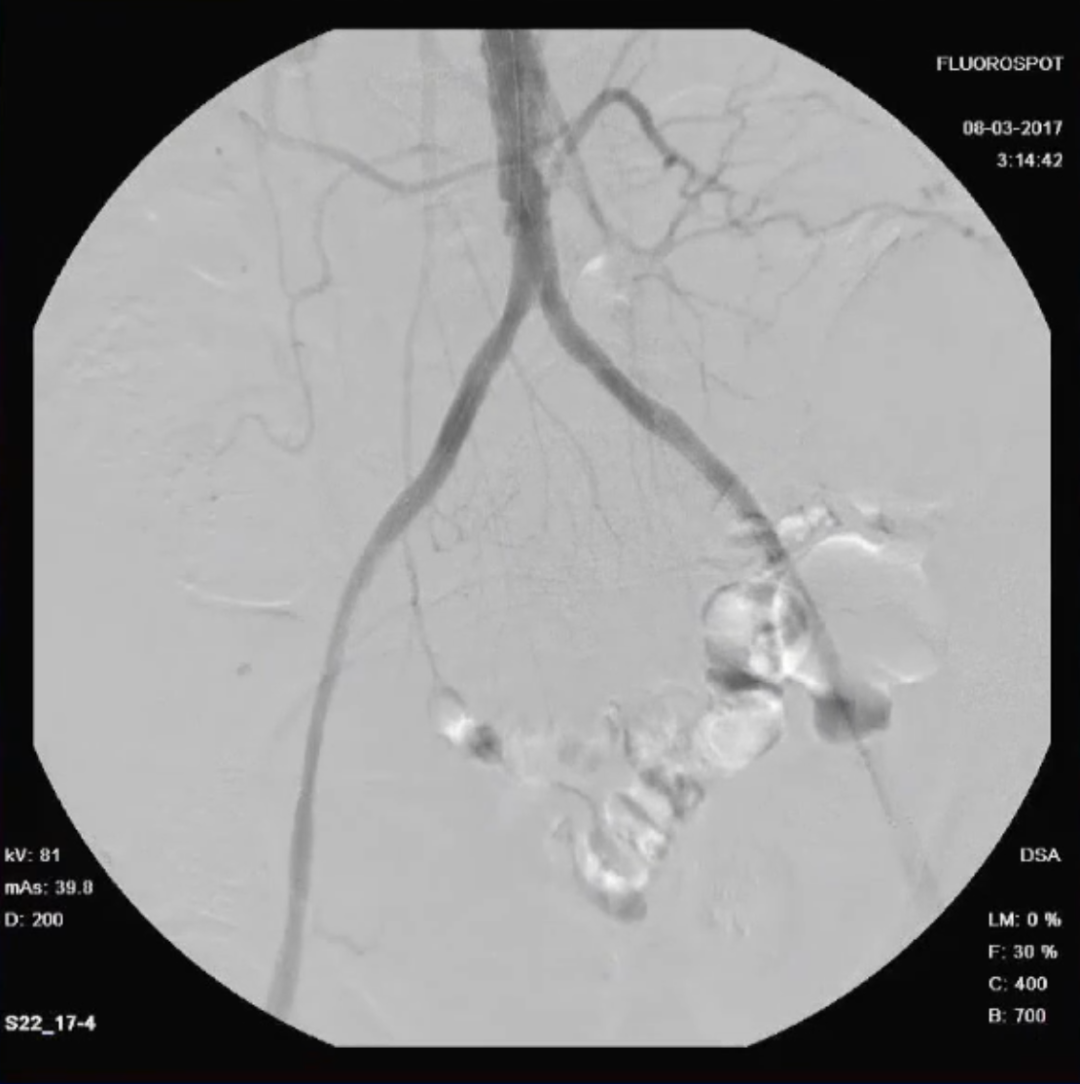

女性、61岁,病史:右下肢无力三个月

预置导管溶栓3天后效果明显

预置导管溶栓7天后效果满意并行支架术